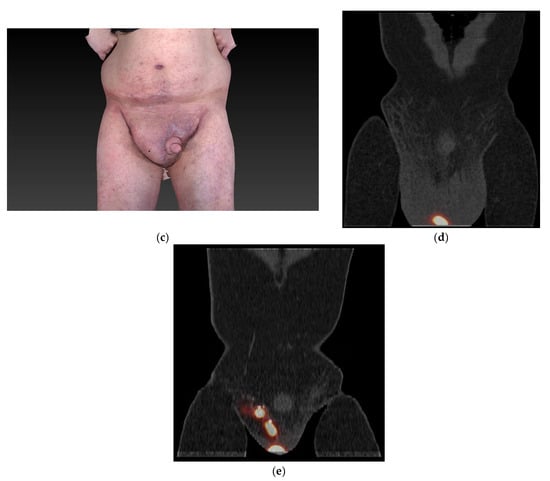

Giant Penoscrotal Lymphedema—What to Do? Presentation of a Curative Treatment Algorithm

3. Results